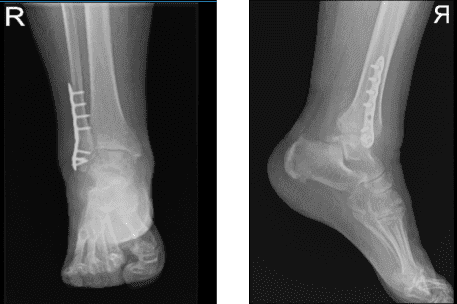

Tiene su radiografía con ella, la revisamos y lo comentamos. Hablamos sobre el dolor crónico de tobillo y la inestabilidad. Repasamos el procedimiento quirúrgico y el no quirúrgico y el paciente pensará en la cirugía.

Se optó por una placa fibular distal de 4 orificios sujeta con hilos K oliva. Al encontrar una posición aceptable en la vista de visión AP y lateral, se fijó la placa en la fíbula usando cuatro tornillos corticales no bloqueantes proximales y cuatro tornillos distales de bloqueo

Tras un mes, sugirió al paciente que hiciera una radiografía para comprobar el estado del tobillo operado. El resultado mostró fractura distal fionar antigua y cicatrizada quirúrgicamente. El paciente no ha recibido fisioterapia. Con el seguimiento constante y el procedimiento RICE, los pacientes se recuperan.